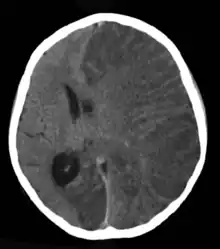

Podem ser encontradas lesões no cérebro através de exames de imagem, como a tomografia computadorizada, mas normalmente tais lesões não são encontradas. O eletroencefalograma (EEG) pode ajudar, mas idealmente deve ser feito durante a crise.